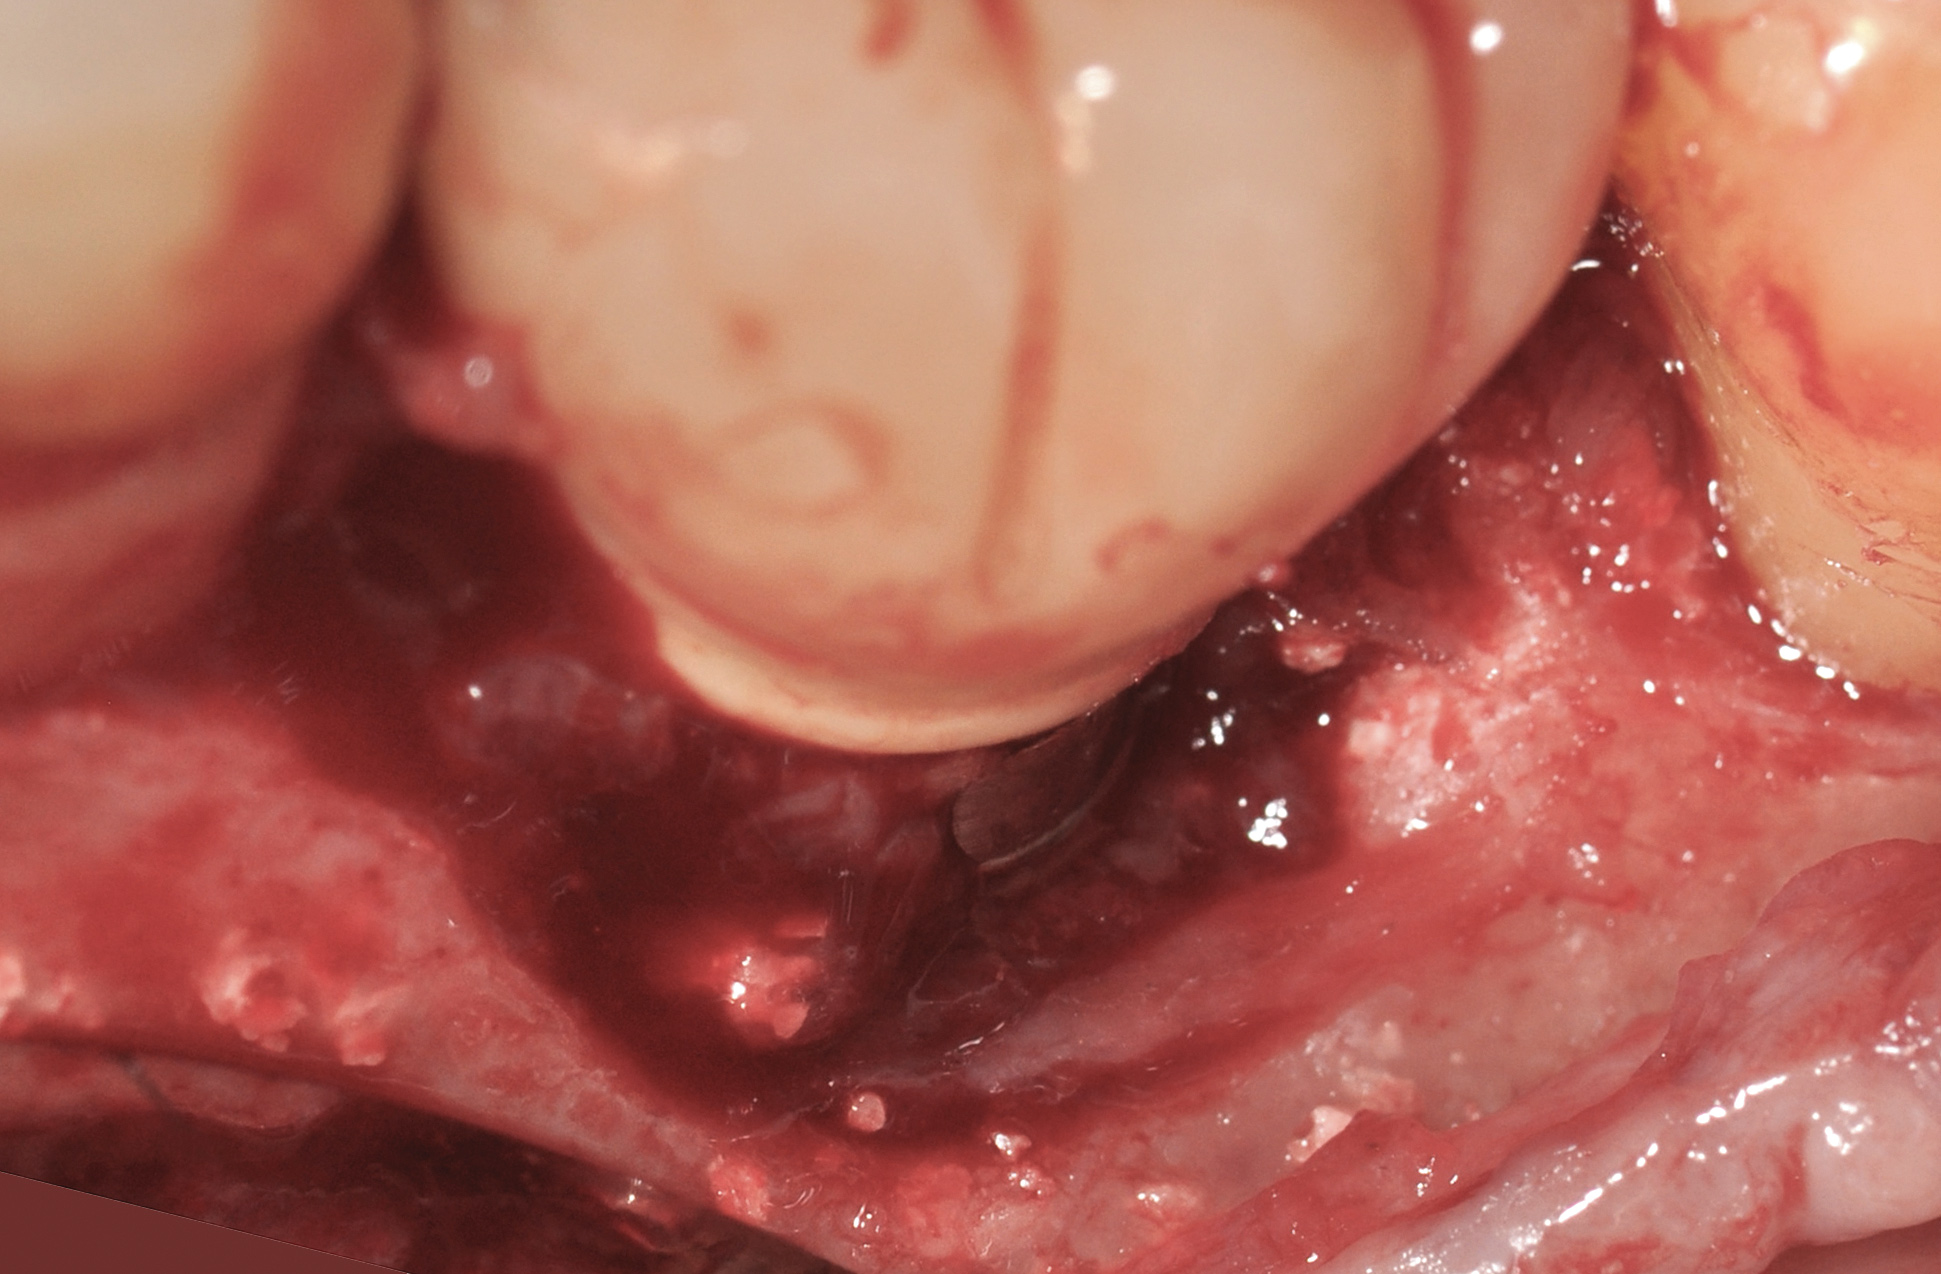

A surgical flap procedure was performed with the intent of thoroughly debriding the granulomatous tissue from the osseous defect (Figure 18 and Figure 19), mechanically and chemically detoxifying the surface of the implant (Figure 20 through Figure 22), and grafting the infrabony component of lesion with bone xenograft (Bio-Oss®, Geistlich Pharma, www.geistlich-na.com) in an attempt to reduce the vertical defect (Figure 23). To concurrently resolve the mucogingival problem, the plan called for placing a dermal allograft (Dermis Allograft, DENTSPLY International, www.dentsply.com) on the buccal (Figure 24) and then replacing the flap (Figure 25).

Fig 20. The implant surface was thoroughly debrided mechanically using a carbon-fiber curette in the grooves between the implant threads.

Figure 20

Fig 21. Meticulous burnishing of the implant surface with a cotton pellet soaked in saline was done to mechanically remove the endotoxin and chemically detoxify the surface of the implant.

Figure 21

Fig 22. Copious irrigation with dilute hydrogen peroxide was used to chemically detoxify the surface of the implant and the bony defect.

Figure 22